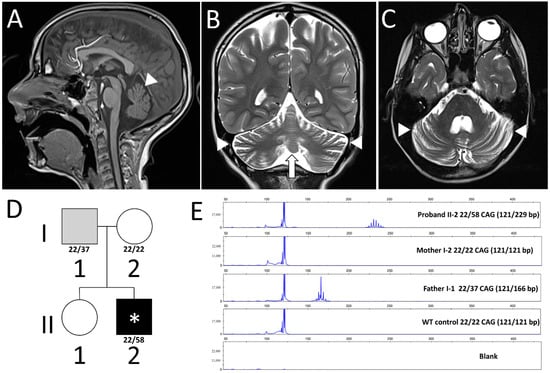

3.1. Case Reports